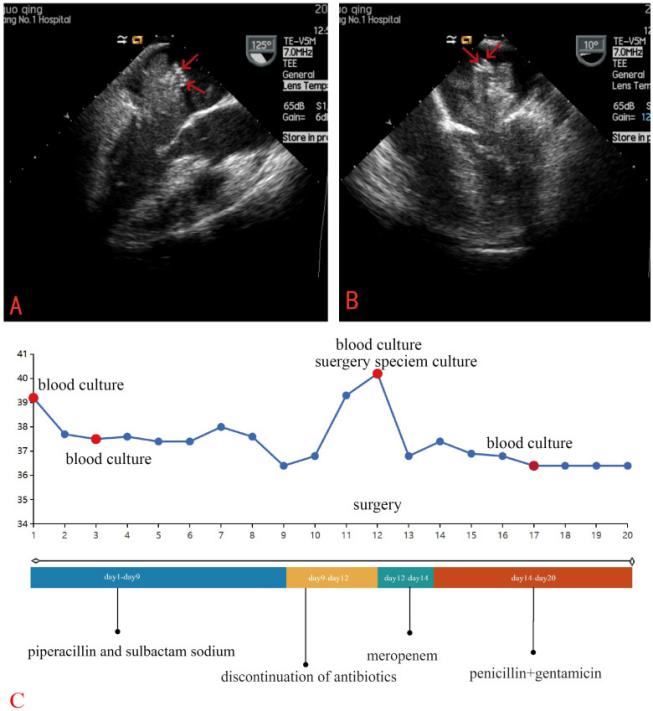

经胸超声心动图和经食道超声心动图显示左心房卵圆窝处一细长不规则肿块,基底约9mm,大小约7cm×3cm。舒张期肿瘤脱垂至左心室,导致二尖瓣梗阻。TEE发现肿瘤表面有点状高回声灶(无彗尾伪影)。这些发现与心房粘液瘤一致。此外,超声心动图检查结果包括左心房扩张、轻度至中度三尖瓣反流、心动过速和左心室射血分数估计为55%。

图2 经食管超声心动图显示,左心房卵圆窝有一个细长的不规则肿块,基底约9毫米,尺寸约7厘米×3厘米,肿瘤表面可见点状回声灶(红色箭头)。(A)左心室长轴视图(B)四腔视图(C)临床时间线